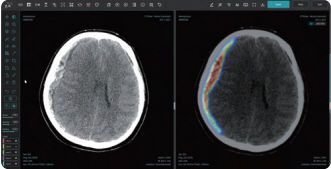

이런 가운데 인공지능(AI) 기반 뇌 질환 진단 기업 제이엘케이(JLK)가 개발한 ‘JLK-SDH’ 솔루션이 미국 식품의약국(FDA)으로부터 인허가를 획득한 것이 재조명되며 주목받고 있다.

JLK-SDH는 컴퓨터 단층촬영(CT)에서 신호강도가 강하지 않아 정상 뇌와 구분이 어려운 아급성(subacute) 혹은 만성 경막하출혈 데이터 학습에 공을 들여 어려운 뇌출혈 진단에 강점이 있다고 회사 측은 전했다. 회사 측은 JLK-SDH 솔루션이 응급 상황에서 의료진에게 신속하고 정확한 진단을 내리는 데 큰 도움이 될 것이라고 설명했다.

제이엘케이 관계자는 "JLK-SDH는 컴퓨터 CT 이미지를 기반으로 지주막하출혈 여부를 빠르게 분석해 의료진의 초기 판단을 돕는 솔루션"이라고 말했다.